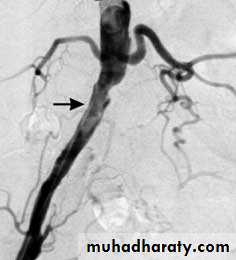

Angiography of buerger disease ((corkscrew))